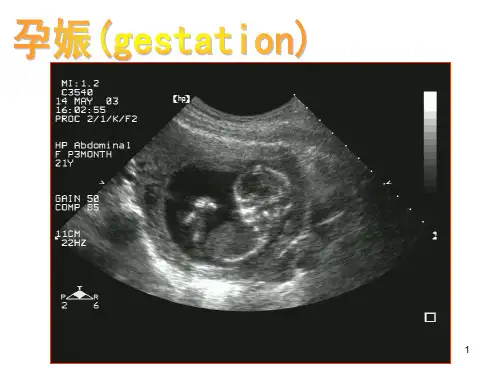

2.妇产科:多普勒在妇产科中有着重要的应用。

它可以评估胎儿的心脏功能和血流,检测胎儿是否有窒息、贫血等问题。

此外,多普勒也用于检测子宫内膜异位症等妇科疾病。

彩色多普勒超声诊断仪在产科中具有不可替代的重要性,在过去的20年里三维超声在产科的应用经历了巨大的发展,从其应用于胎儿大脑、面部和心脏解剖学的研究到其改进胎儿器官和四肢的体积和胎儿出生体重的估计,此外,还可通过其定量评估胎儿器官和胎盘的血管造影模式【1】;英国有建议提倡使用子宫动脉多普勒超声检查和多普勒的脐动脉、中脑动脉和静脉导管,以监测和提供生长受限胎儿的分娩时间。